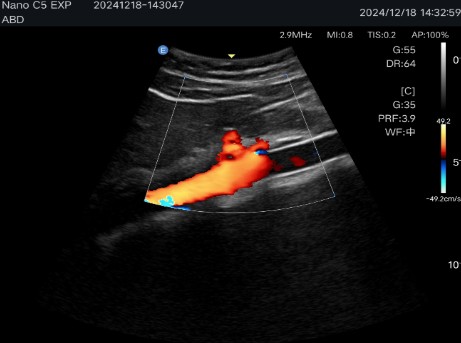

Multiple imaging modes: Includes B-mode, C-mode, M-mode and Pulsed Doppler (PW), ensuring precise visualizations for various clinical applications.

Abdominal diagnostics, obstetrics and gynecology: Allows detailed evaluation of internal organs and structures.